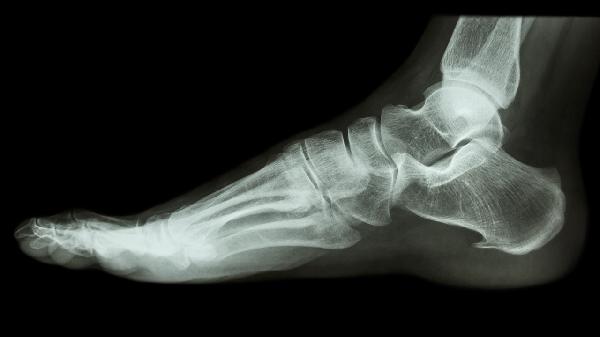

对于移位明显的关节内骨折、开放性骨折或保守治疗失败的情况,需考虑手术治疗。常用术式包括切开复位内固定术,使用螺钉或钢板对骨折块进行牢固固定。术后仍需配合石膏外固定,并定期复查X线片观察骨折愈合情况。手术治疗能实现解剖复位,最大程度恢复足部功能。